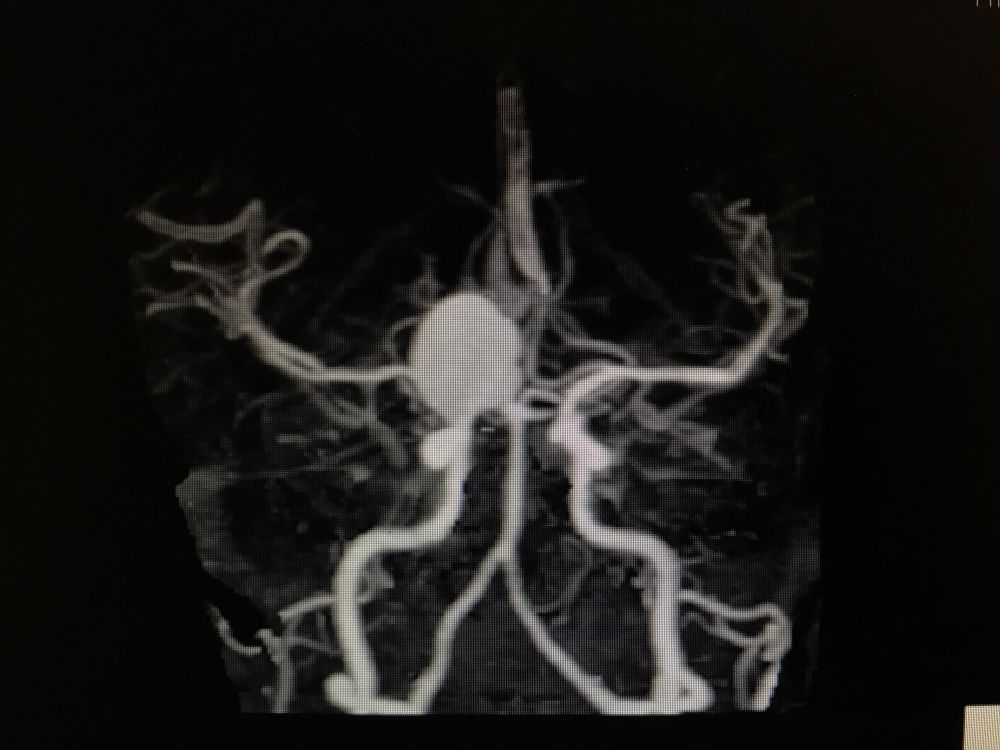

入院后完善DSA检查提示颅内多发动脉瘤:右侧颈内动脉眼段大动脉瘤(约18*19mm,瘤颈6.6mm),左侧眼动脉段及床突段动脉瘤。和家属沟通病情,告知介入和开颅手术风险利弊后,患者家属选择开颅动脉瘤夹闭手术治疗。进一步行DSA+CT融合,模拟手术入路视角。

术前MRA和CTA

右侧眼动脉瘤

左侧眼动脉段及床突段动脉瘤

夹闭后复查DSA

再次探查动脉瘤发现瘤体表面张力明显下降,探针分离瘤颈,以2枚直动脉瘤夹792+760夹闭瘤颈。解除球囊阻断后,动脉瘤表面张力无回升,穿刺瘤体无活动性出血。荧光造影提示瘤体无显影,载瘤动脉血流通畅,无明显狭窄,各分支保留完好。切除部分瘤体,视神经减压。DSA复查提示动脉瘤夹闭满意,全脑血管通畅后关颅。(球囊阻断时间约10分钟)